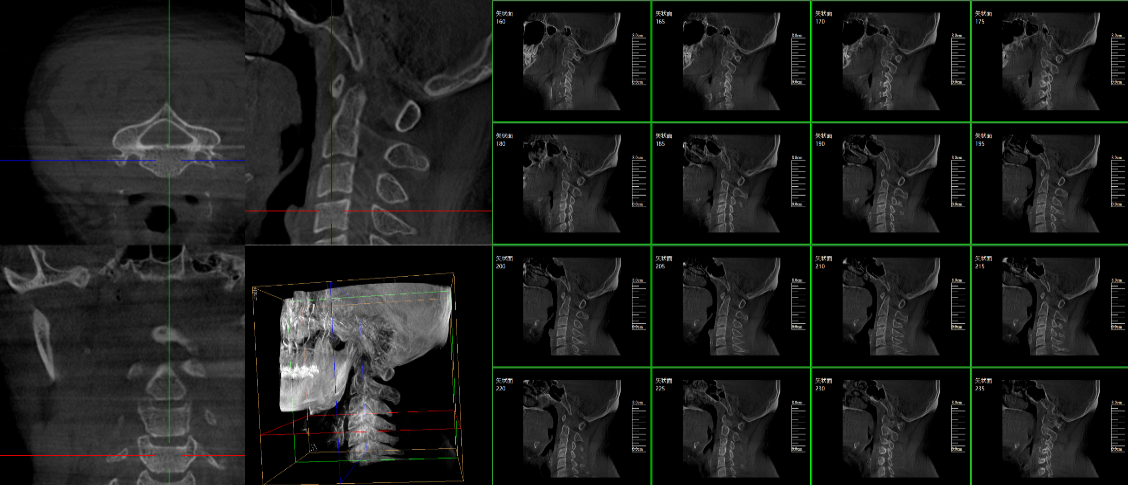

脊柱外科的应用:有研究表明,在三维c型臂图像引导的下颈椎或胸椎后路螺钉置入术中,螺钉正确置入率可达92.7%,在三维c型臂图像引导的椎间孔腰椎椎间盘融合术中,术者被辐射总量明显降低。此外三维c型臂可以搭配骨科手术导航和机器人使用,能将该过程智能化和准确化,进一步提高螺钉的植入率。

截骨矫形外科中的应用:胸腰段是脊柱应力相对集中区域,因此,该节段更易发生骨折,且骨折术后更易并发角状后凸畸形,大多数患者都需二次手术矫正。他们认为术中三维c型臂辅助后路螺钉置入并半椎体切除矫形治疗儿童先天性脊柱后突畸形患者时,螺钉置入精度高且安全,截骨矫正效果满意。

创伤外科的应用:由于创伤外科的患者多数为急、重症患者,以致术前准备时间较短,很多都需行急诊手术,三维c型臂可以在术中实时重建三维图像,使手术医生对一些复杂骨折更加充分的了解,并且能够在术中即时校正螺钉的位置,更加精确地置入固定器材,减少术中及术后发生并发症的几率,极大限度地缩短螺钉置入时间。